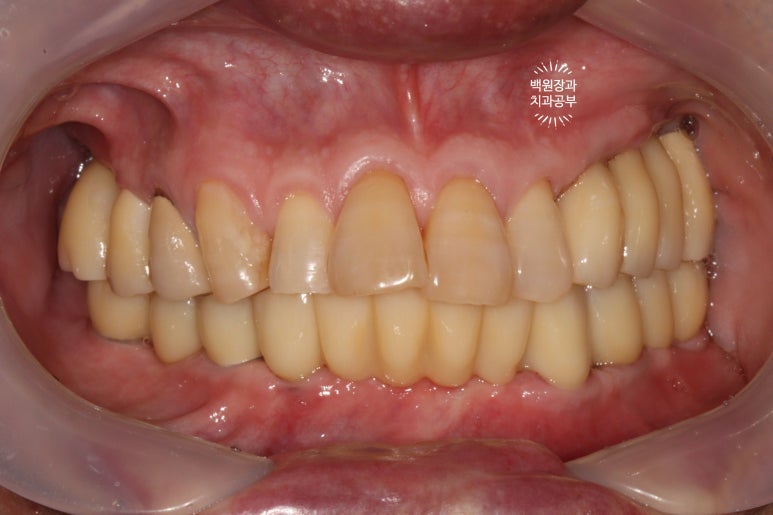

드디어 전체임플란트가 완성되었습니다!!

짜잔!!! 정말 비슷한 색상으로 제작이 잘 되어왔습니다.

최종 크라운을 연결하고나니 그렇게 깔끔할수가 없네요.

이렇게까지 제작해드리는데, 위턱에는 4개의 임플란트 아래턱에는 6개의 임플란트만 사용하였을 뿐입니다.

다행이라면 60대 남성분임에도 불구하고, 악궁이 작으신 편이라 12개의 치아만으로도 충분히 불편하지 않게 식사가 가능하셨습니다.